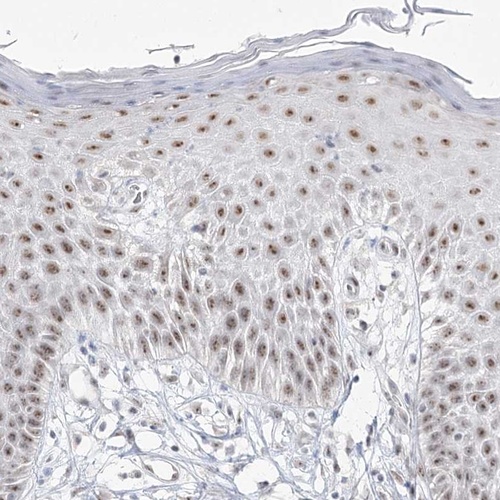

Immunohistochemical staining of human vulva/anal skin shows moderate nucleolar positivity in squamous epithelial cells.